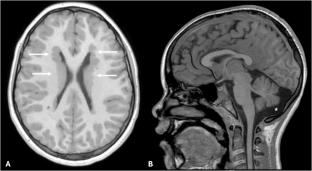

Filamin A (FLNA) is an actin-binding protein involved in cytoskeleton organization and cell migration. Loss-of-function (LOF) variants give rise to a wide variety of symptoms with periventricular nodular heterotopia (PVNH) and epilepsy as the most common features. FLNA deficiency manifests as a multisystemic disorder with abnormalities of connective tissue and involvement of the cardiovascular, pulmonary, gastrointestinal and hematological system. Affected individuals need a multidisciplinary follow-up, but guidelines are lacking. Here, we present findings from a monocentric cross-sectional cohort study as a basis for improving clinical practices and surveillance for individuals with FLNA deficiency.

24 index patients with FLNA deficiency were identified. In the cohort, 23 patients exhibited clinical features of PVNH, while one individual presented with congenital pulmonary airway malformation (CPAM). The incidence of clinical features such as epilepsy (84%) and cardiovascular involvement (56%) align with previously published cohorts. Systematic multidisciplinary follow-up, particularly regular cardiological screening, was lacking in a significant number of individuals. Additionally, lesser-known symptoms such as constipation and thrombocytopenia were underreported, highlighting the need for comprehensive phenotypic assessment in FLNA deficiency.